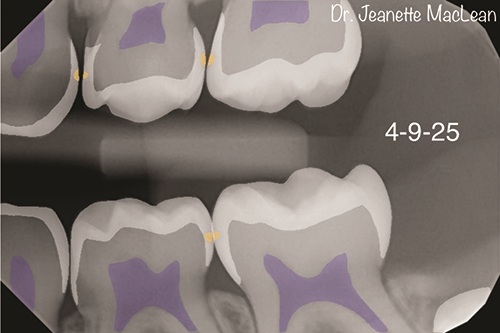

Figs. 2a and 2b: Overjet identifies incipient caries lesions, highlighted in yellow. Surgical intervention is not indicated at this time. Nonsurgical treatment with silver diamine fluoride is offered and accepted by parent.

Figs. 4a and 4b: Overjet confirms the incipient lesions are stable after treatment with silver diamine fluoride (Advantage Arrest, Elevate Oral Care). The lesions between the mandibular right primary molars are no longer detectable.